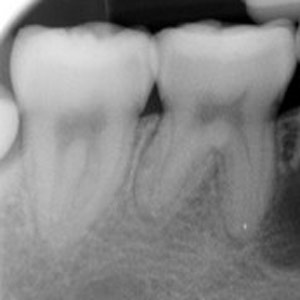

NON-SURGICAL

Oftentimes, our patients need non-surgical treatments that require minimal intervention. This intertwines with our belief that preventative maintenance and regular dental care can minimize the need for surgeries. You can rest assured that our highly trained and experienced team consistently provides the highest quality endodontic treatments and assistance available in the North Shore.